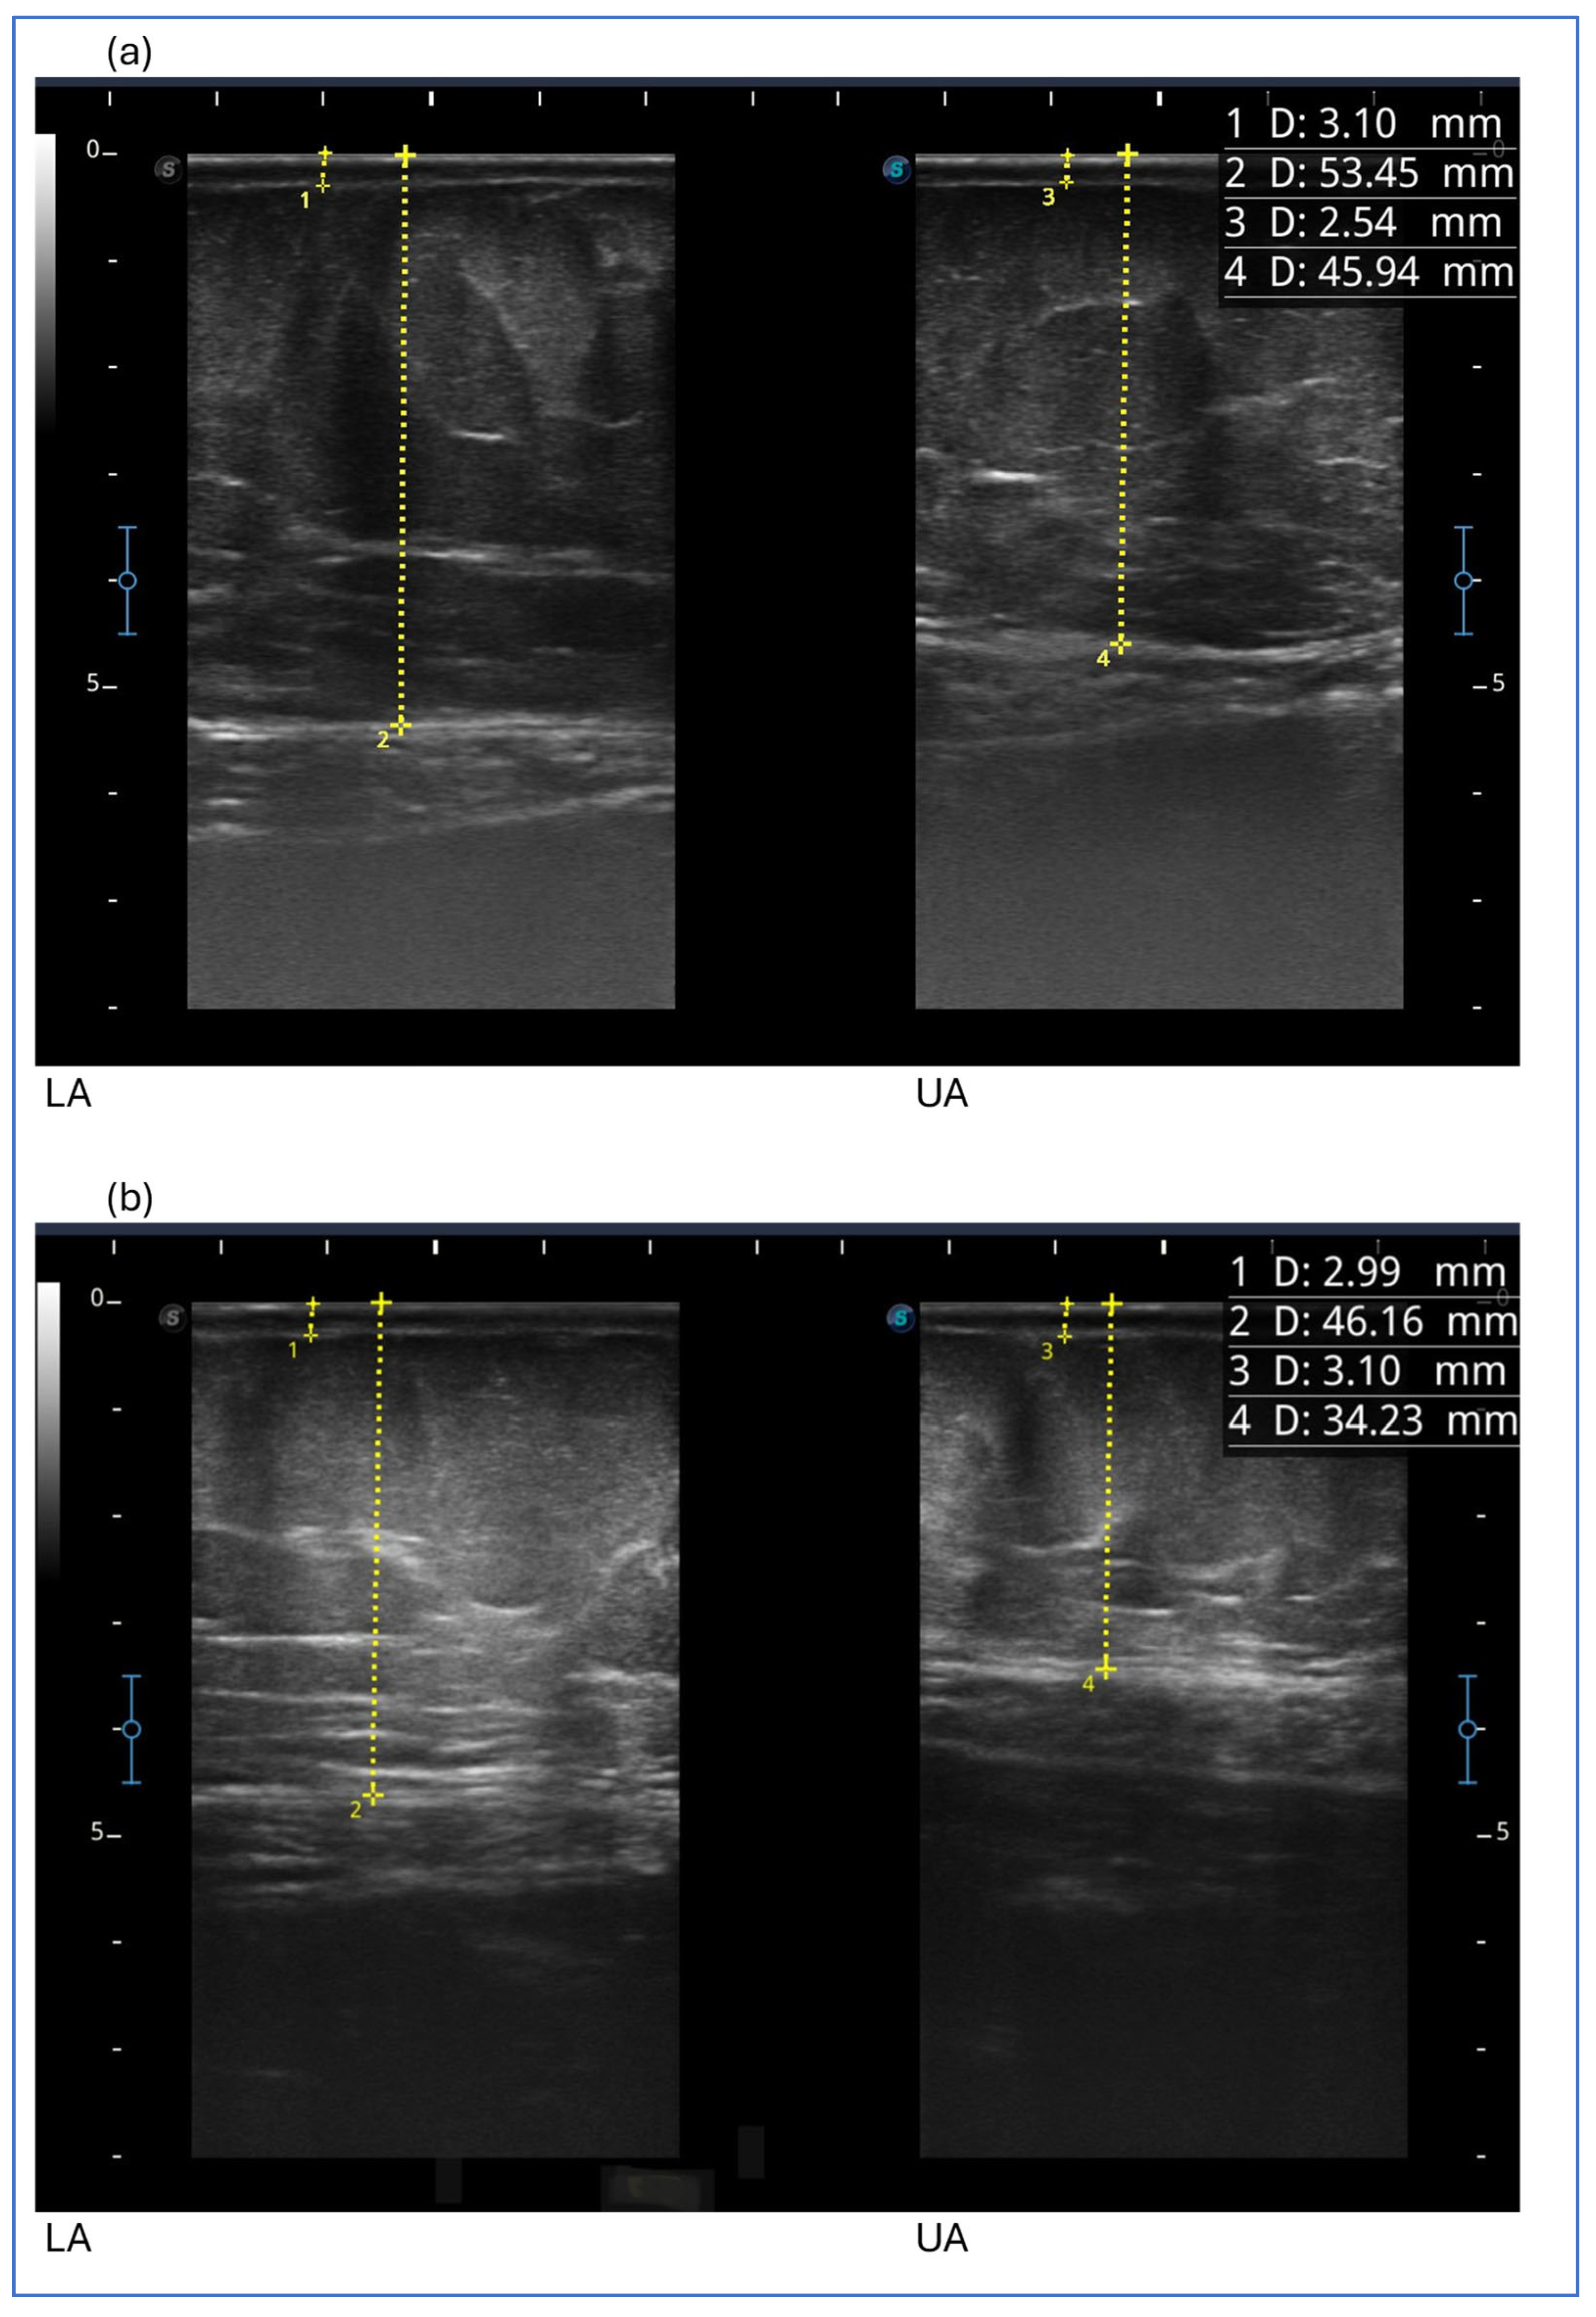

After the first 3 months, we detected a reduction in the thickness of subcutaneous adipose tissue at all levels examined in the lower limb, abdomen and upper limb. Then, the thickness of subcutaneous adipose tissue generally increased, with the exception of the upper anterior third of the thigh and upper abdomen, which showed a further reduction. It remained unchanged at the two points of the lower limb (medial upper third of the leg and anterior middle third of the thigh) (Figure 4).

The figure shows ultrasound measurements at the beginning of the study in the image above (a) and at the end of the study in the image below (b) for case report 4. The images refer to the lower abdomen (LA) and upper abdomen (UA). The yellow dotted line represents the measurement of the thickness of the skin, which includes the dermal and epidermal layers (1 D and 3 D), and of the subcutaneous adipose tissue (2 D and 4 D), which includes all the tissue from the skin to the muscular fascia.